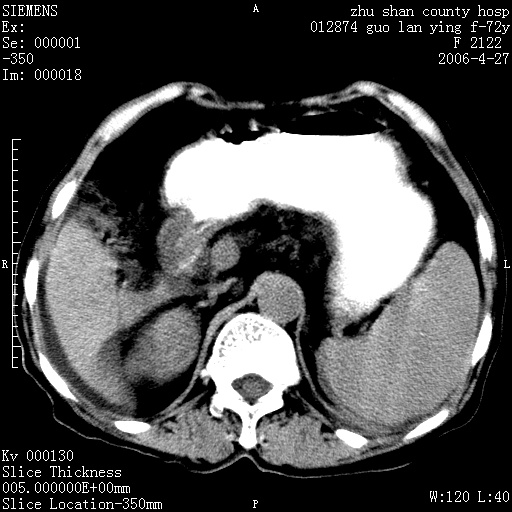

平扫所见:胆囊区两点壮高密度影,灶周有伪影{请问楼主患者有手术病史?}。肝实质内未见明显异常{建议强化或mri}.腹腔有少量积液,脾明显增大.右肾形态似不规则?

腹腔内示积液征,脾脏略增大,肝脏由于运动伪影较多,影响观察,内未见明显高密度区,胆囊内示两处高密度结石。胃窦部壁轻度增厚。另外,肝脏的前缘似有游历气体。不知病人的临床如何?有必要做胃的检查,还有,看看骨窗是否有腹腔游离气体还是肠管影响的。

肝脏缩小,脾脏增大,肝脾外缘及胆囊窝液性密度影,肝脾ct值正常,胆囊区见两个类圆形高密度影,下腔静脉前方类圆形软组织密度影为肝脏岛叶,胃幽门区见软组织密度影,十二指肠钡剂充盈不好.

1:腹水2:胆囊结石3肝硬化?(不确定,请结合临床)4幽门区占位?(建议胃肠透视)

肝硬化,脾大,少量腹水

肝硬化、腹水、脾大,胆囊结石可以肯定。只是肝右叶两个低密度有必要增强确定一下;排除小肝癌。